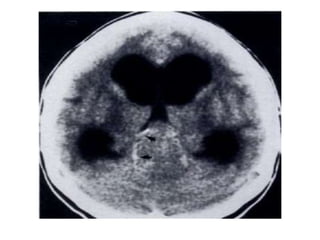

Axial nonenhanced CT shows a large pineal region mass with resultant hydrocephalus ,

the pineal calcifications are exploded toward the periphery (arrows)

b) Pineoblastoma : -Highlymalignant PNET (Primitive Neuroectodermal Tumors) -In patients with trilateral retinoblastoma, Pineoblastoma may develop in patients with familial and or bilateral retinoblastoma -(Exploded calcifications) along outside of mass (peripherally), unlike germinoma which engulfs and induces calcification of the pineal gland -Dense enhancement -Larger, more heterogeneous with much greater propensity for local invasion and CNS dissemination

• 60.

Axial nonenhanced CTshows a large pineal region mass with resultant hydrocephalus , the pineal calcifications are exploded toward the periphery (arrows)